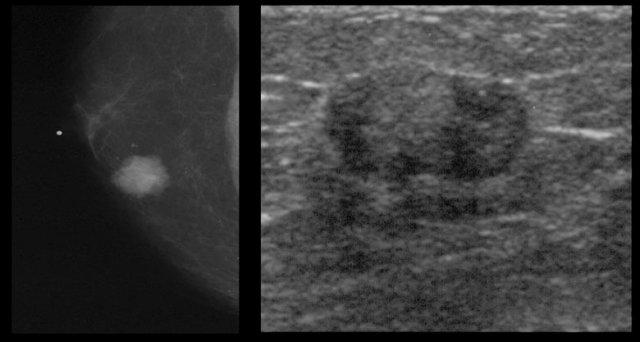

Bên trái là nhũ ảnh và hình siêu âm của một bệnh nhân có gynecomastia thể nốt tuyến.

Lưu ý tổn thương nằm ngay dưới núm vú.

Hình siêu âm cho thấy hình ảnh điển hình của gynecomastia: một khối giảm âm với bờ thùy múi hoặc thậm chí có gai.

Nếu đây là hình ảnh của một phụ nữ, bạn sẽ nhận định đây là một khối có vi thùy múi và gai, tức là Birads IV hoặc V.

Ở nam giới, đây là hình ảnh điển hình của gynecomastia.

Bên trái là cùng hình siêu âm đó, nhưng ở tư thế bình thường.

Lưu ý hình ảnh trông ‘ác tính’ như thế nào.